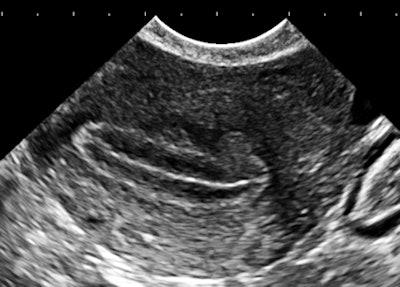

The importance of image contrast is demonstrated in these endovaginal images of a 36-year-old nulliparous woman with heavy and irregular periods due to adenomyosis.

| Above and below: Endovaginal images of a 36-year-old nulliparous woman with heavy and irregular periods due to adenomyosis. |

Adenomyosis (i.e., gland tissue in muscle) occurs when the integrity of the endometrial boundary is disrupted and rapidly growing, vigorous endometrial cells migrate from the city to the myometrial suburbs. Glandular tissue is highly vascularized, leading to the typical 2D Doppler findings with the clinical presentation of heavy, often painful menstruation with clots. There may be small secretory cysts.

The border zone irregularities reconcile the ultrasound findings with pathology and with the classic sign of hysterosalpingography for this condition. This is a grayscale contrast issue. Over the years, I have come to regard contrast as the most important determinant of image quality for all applications of ultrasound.